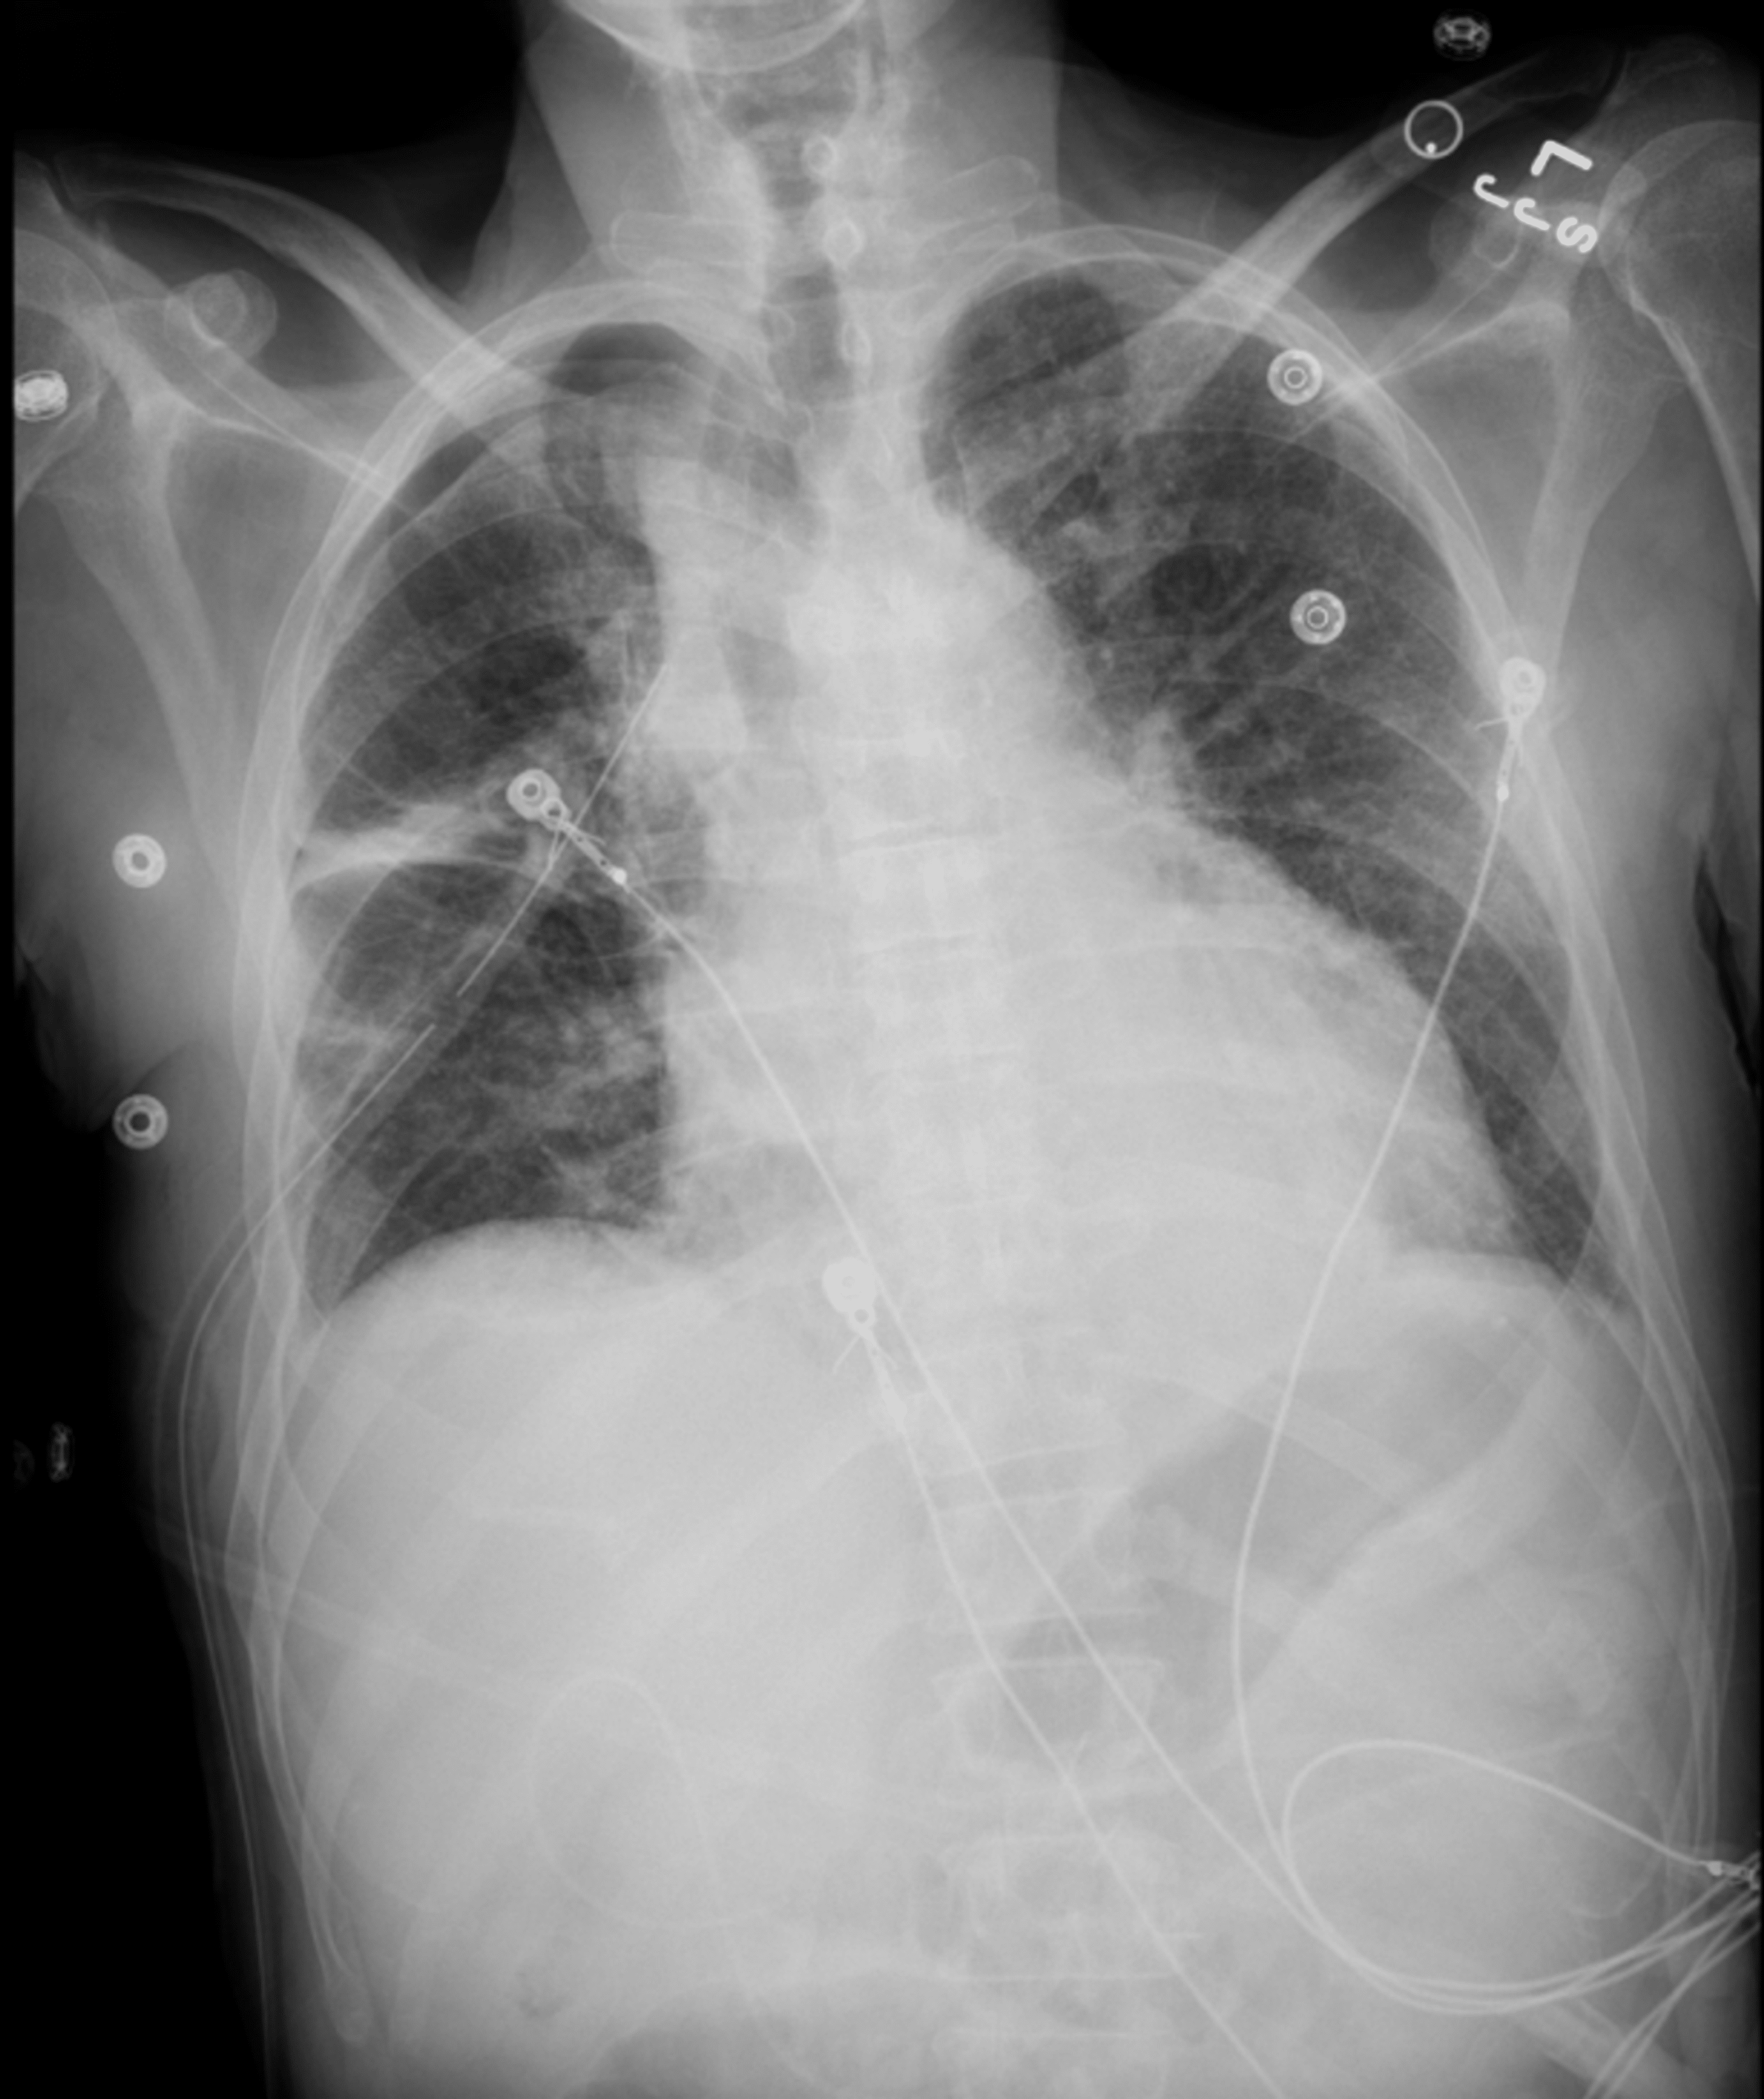

Xray chest and abdomen on day 3 of bite after insertion of chest tube Post Chest Tube Removal X Ray For patients in extremis, expeditious. In addition, for proper chest tube care, chest tubes can be used to instill fluids into the pleural space, such as chemotherapy. blood and prevent cardiac tamponade. Post Chest Tube Removal X Ray.

Chest Xray after the placement of the chest tube Download Scientific Post Chest Tube Removal X Ray blood and prevent cardiac tamponade. For patients in extremis, expeditious. In addition, for proper chest tube care, chest tubes can be used to instill fluids into the pleural space, such as chemotherapy. Post Chest Tube Removal X Ray.

Chest Xray showing a normal Xray 2 hours after chest tube removal Post Chest Tube Removal X Ray In addition, for proper chest tube care, chest tubes can be used to instill fluids into the pleural space, such as chemotherapy. For patients in extremis, expeditious. blood and prevent cardiac tamponade. Post Chest Tube Removal X Ray.

Chest xray after chest tube removal with apical pneumothorax and Post Chest Tube Removal X Ray In addition, for proper chest tube care, chest tubes can be used to instill fluids into the pleural space, such as chemotherapy. blood and prevent cardiac tamponade. For patients in extremis, expeditious. Post Chest Tube Removal X Ray.